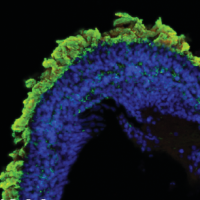

A complementary approach to understanding genes important in optic fissure closure in humans is the laboratory use of animal models. We use mouse and zebrafish models to better understand how genes are regulated during the course of optic fissure closure. Specific mutant mouse strains are also being investigated to discover genes that might cause coloboma in humans. These studies have identified that two zinc finger proteins, Nlz1 and Nlz2, regulate optic fissure closure, perhaps through a Pax2-dependent mechanism. We are currently trying to understand the developmental role of these and other genes from our screen in the normal process of optic fissure closure and to search for causative mutations in humans.